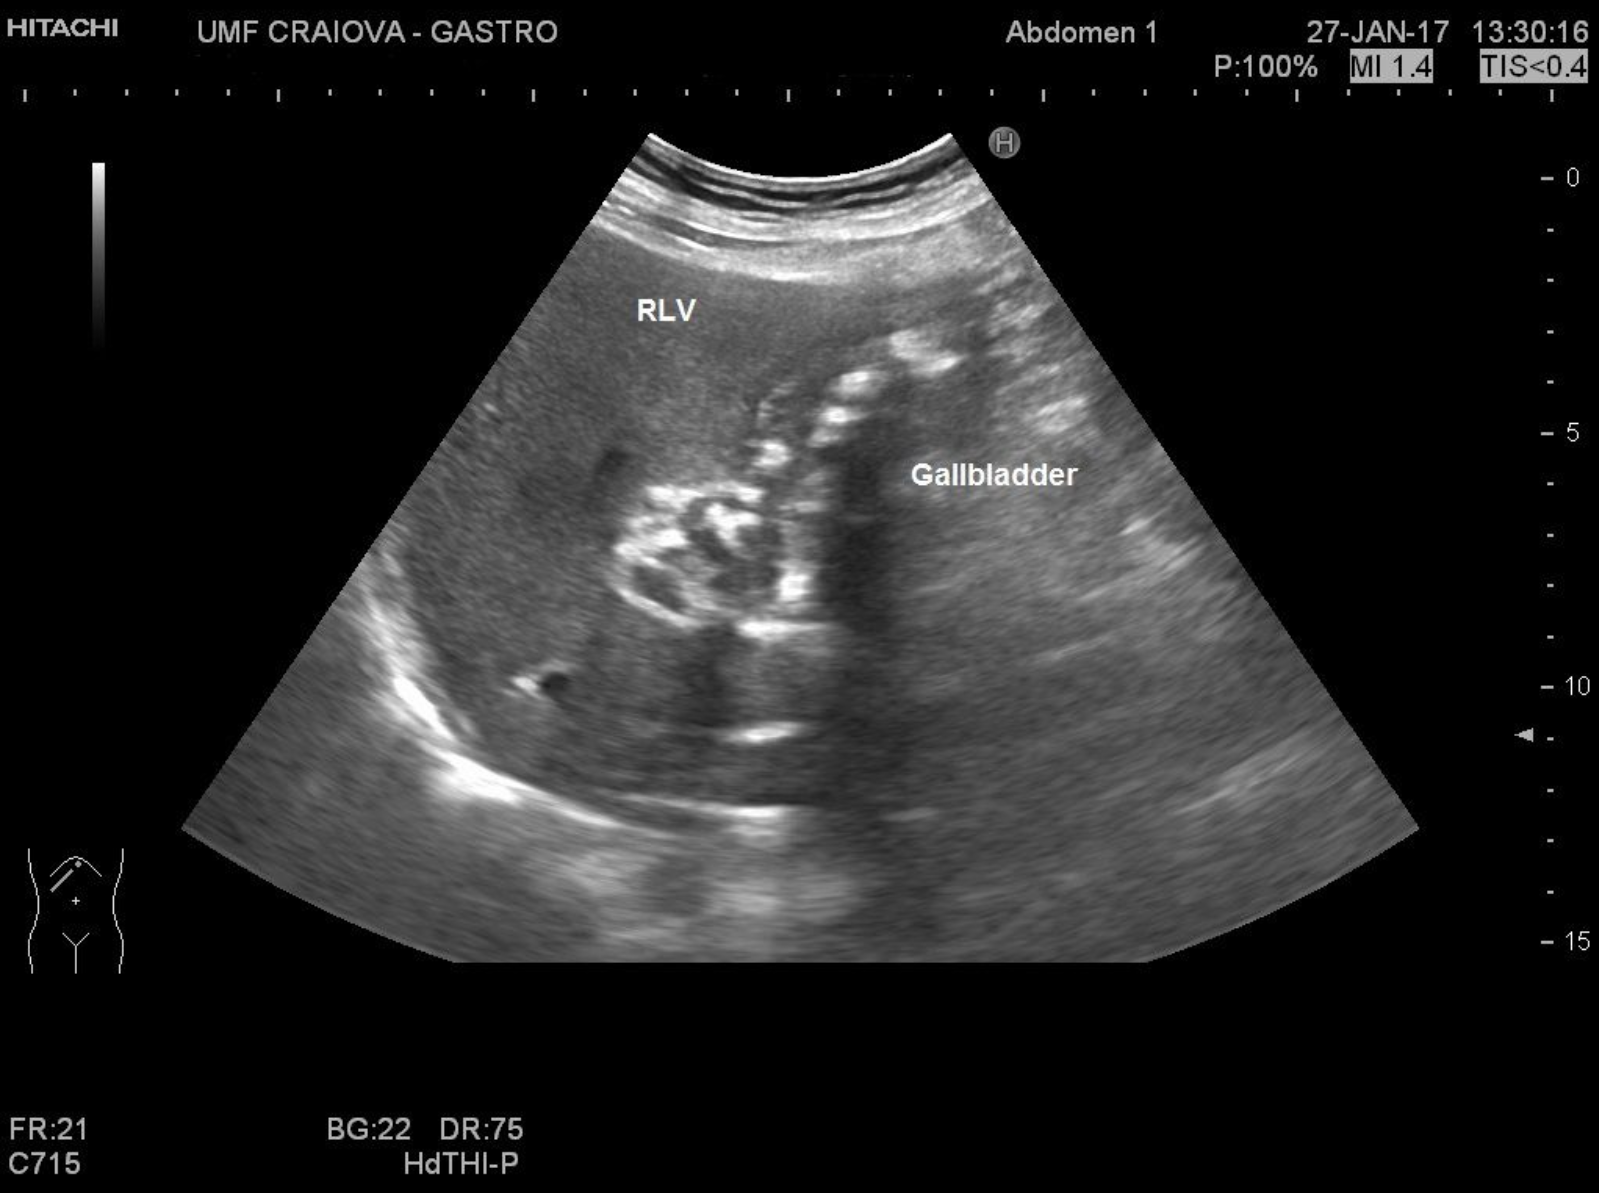

TITLE:  Gallbladder carcinoma

65 year old male. Dilatated gallbladder, inhomogenous structure of the walls, with an important amount of sludge and gallstones.

gallbladder ultrasound, gallbladder carcinoma